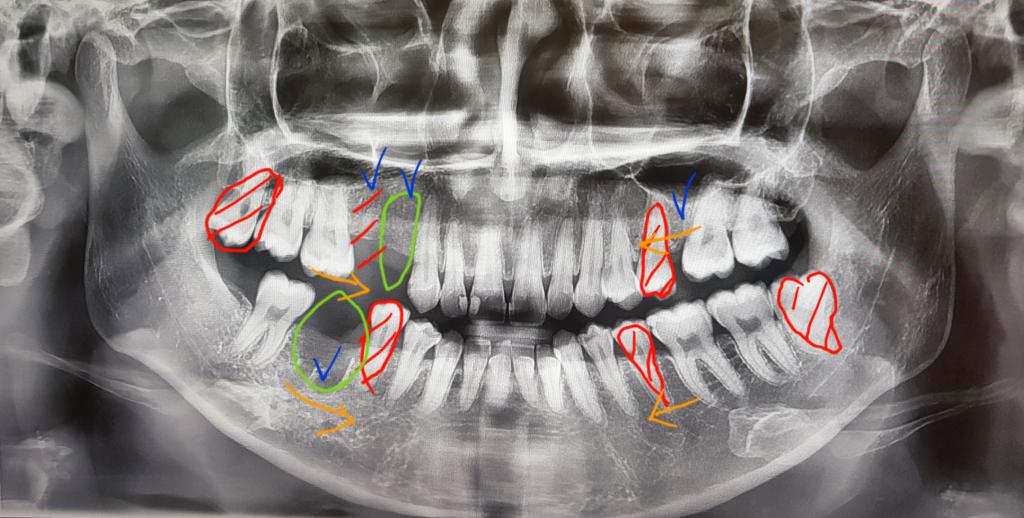

치아상태는 어렸을때부터 관리를 못해서 4개치아를 발치했어요..

파란색표시되어있는 부분이 치아를 발치한 자리구요

빨간색표시가 발치해야하는 치아입니다

연두색표시가 임플란트해야하는 곳이구요..

1. 첫번째 상담에선 위아래 5번째 치아 발치 후

임플란트 두개를 해야한다고 하셨어요

스크류도 왼쪽위쪽에 해야할수있다고 하셨구요

위에보단 아래가 많이 들어가 무턱에 효과를 크게 볼 수 있다고

하셨습니다..

2. 두번째 상담에선 위에 치아 4번, 아래치아 5번발치 후

임플란트는 하나만 하고 아래쪽 임플란트대신

작은 어금니랑 큰 어금니를 옮겨서 위에 큰 어금니 두개랑

교합을 맞춘다고 하셨어요..

임플란트 개수가 줄어들고 제 치아를 살릴수있어서 좋은방법같지만

어금니 하나만으로 과연 괜찮을까 나이먹어서 힘들진 않을까 걱정이 큽니다..

3. 세번째 상담에선 위엔 4번째 치아, 아랜 5번째 치아 발치 후

임플란트 두개 식립해야한다고 하셨어요

무턱이라 입이 최대로 들어가는 방법이라고 하셨지만

위에 4반째 치아를 발치하게 되면 5번치아 뒤에도 발치했던 곳이

치아가 무너져 약간 틈이 있는데 옥니처럼 너무 많이 입이 들어가는게 아닐지 걱정입니다

그리고 위랑 아래랑 다른 치아를 뽑아도 괜찮은지 걱정이구요..